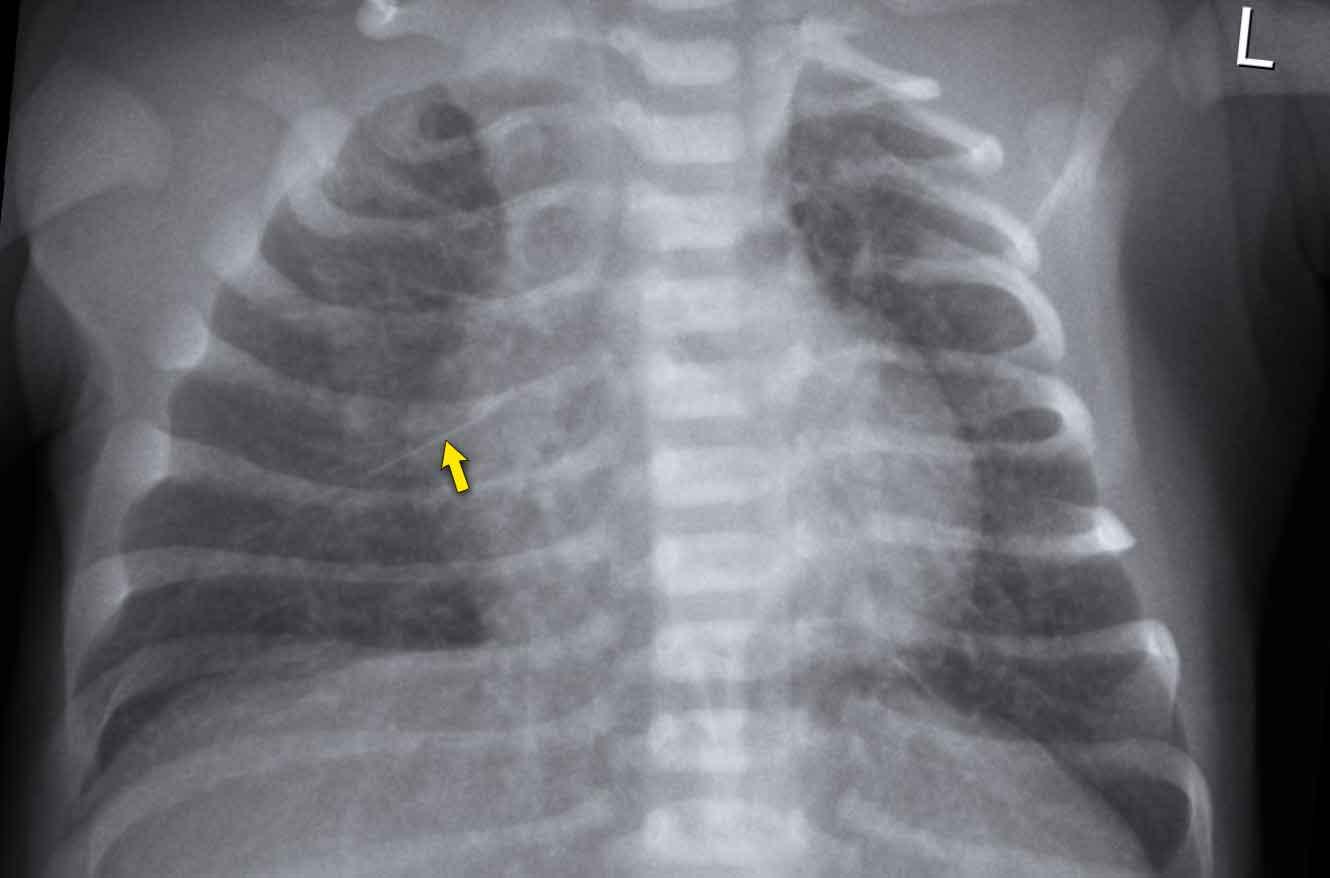

Imaging

- Mild increased lung volume.

- Interstitial edema resulting in perihilar linear densities.

- Subtle enlargement of the cardiac silhouette.

- Pleural effusions and fluid in the fissures.

- The radiological findings may be asymmetrical.

Trẻ sơ sinh 41 tuần tuổi thai. 24 giờ tuổi.

Suy hô hấp, không hỗ trợ thở máy

Image

- Marked

hyperinflation of both lungs - Increased

vascular markings and interstitial markings - Some interfissural fluid (arrow).

Spontaneous improvement within 48 hours.